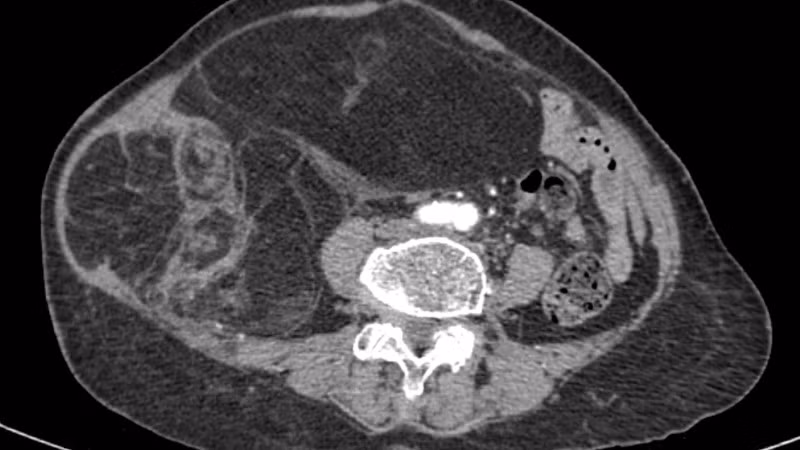

Hình ảnh phim chụp CT ổ bụng của người bệnh.

Trước đó, người bệnh (76 tuổi) nhập viện do bụng to nhanh, căng tức, biến dạng vùng hạ sườn-mạn sườn phải trong khoảng 3 tháng gần đây. Kết quả khám lâm sàng và chẩn đoán hình ảnh cho thấy có khối choán chỗ sau phúc mạc, kích thước 28x15cm, cấu trúc hỗn hợp tổ chức mỡ-đặc, đè đẩy tạng trong ổ bụng nhưng không có dấu hiệu xâm lấn các tạng lân cận. Kết hợp lâm sàng và hình ảnh học, bệnh nhân được chẩn đoán sarcoma mỡ sau phúc mạc.